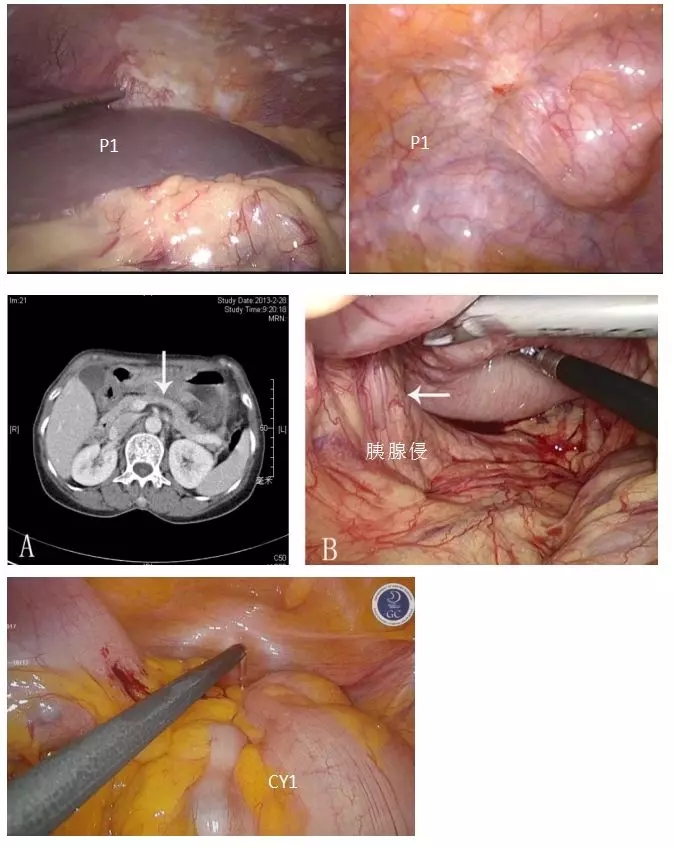

通过腹腔镜分期可以判断是否存在腹膜转移,补充其它分期方法的不足,提供精确的临床分期(cTNM),还可以判断肿瘤切除可能性(T4b,结合影像学)。根据探查结果分为三类,P0,CY0;P0,CY1;P1(图5)。

图5. 根据腔镜探查结果,可帮助对胃癌精准分期